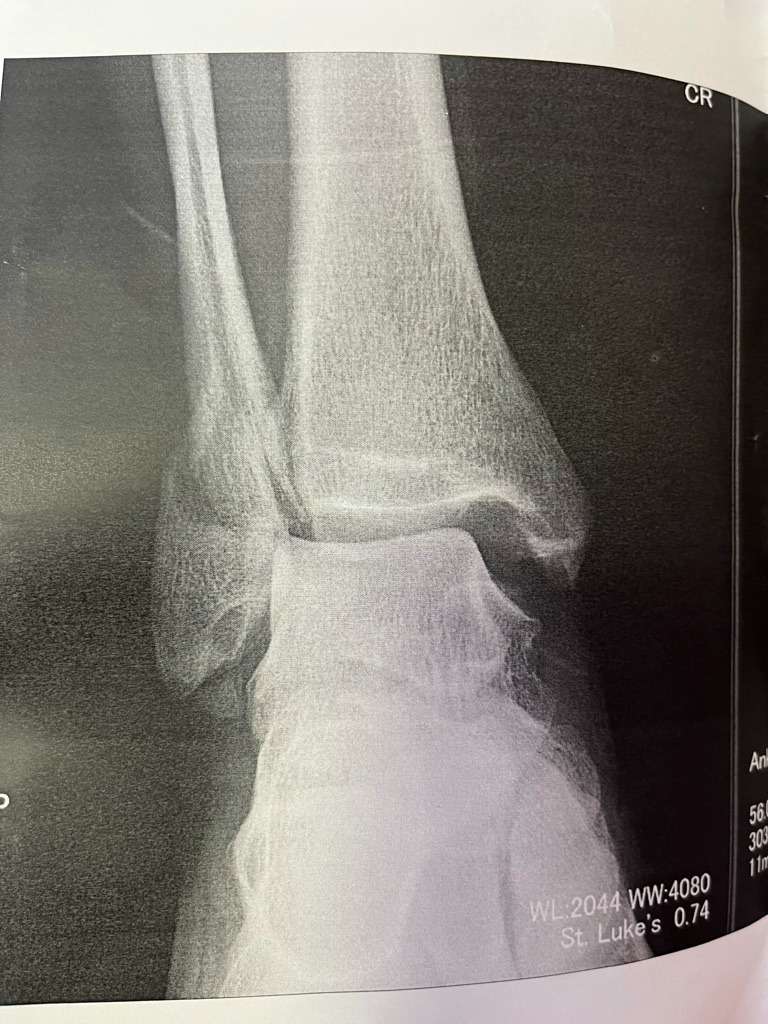

右足首、腓骨遠位端の骨折と脱臼。

そのまま救急搬送、翌々日に整形外科で入院、手術。

骨折部にプレートとボルトを固定し、術後4日で退院。